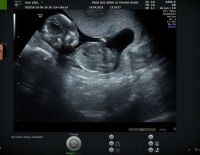

Siêu âm tuần 32 – Mốc siêu âm quan trọng trước kỳ sinh

Siêu âm tuần 22 – Thời điểm tốt để kiểm tra dị tật thai nhi

Giải đáp: Thai nhi 4 tuần tuổi có siêu âm được không?